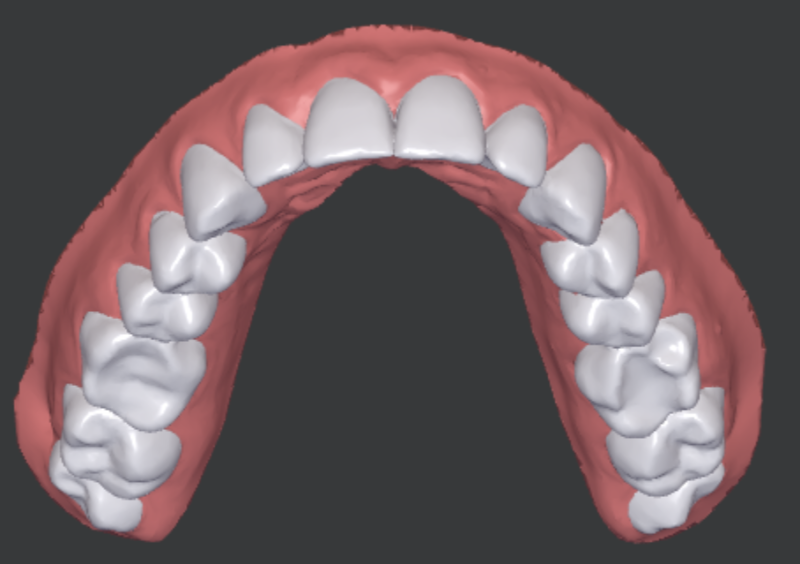

Atténuer l'encombrement antérieur dans les deux mâchoires (voir la simulation des résultats du traitement dans la figure 1)

Maintien des segments buccaux de classe I, obtention d'un overjet et d'un overbite normaux et d'une occlusion fonctionnelle.

Mâchoire supérieure : Protrusion 11, 21, dérotation 14, 13, 11, 21, 23, 24, translation minimale m/d 14-13, 21-24, torque de la couronne 13, 11-24, bascule de la couronne 13, 12, 21-24, intrusion 12, 11, 21, 22, 24, extrusion 13, 23 pour niveler les dents antérieures.

Mâchoire inférieure : Dérivation de 44-34, intrusion 43, 42, 33, 34, translation l/b 44-31, 33, 34, translation m/d 44-33, basculement de la couronne 43, 41-33 et torque de la couronne 43-33.